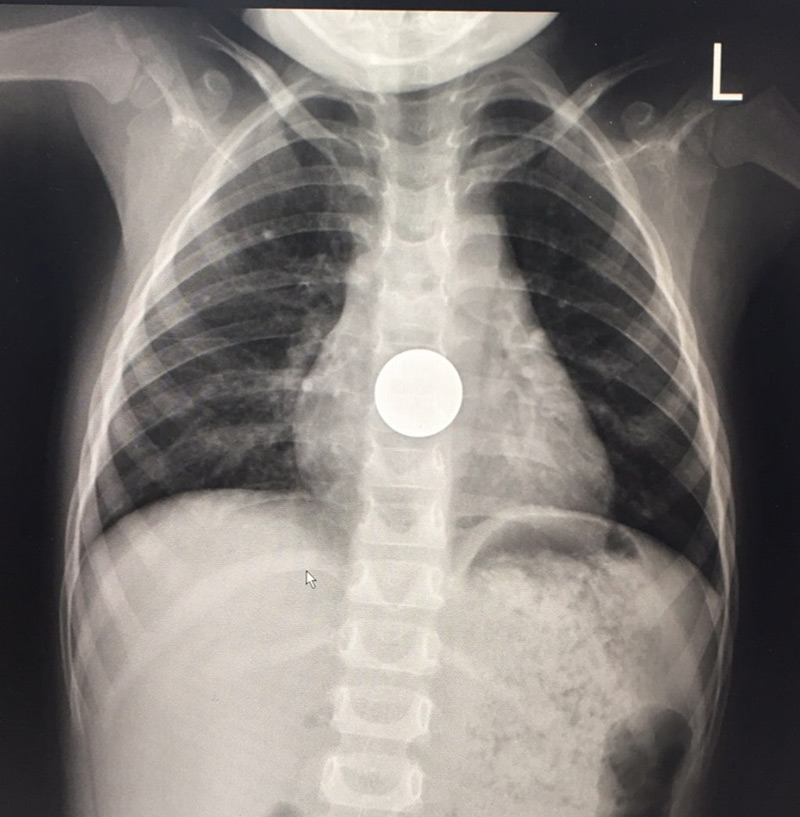

แพทย์เวรห้องฉุกเฉินสันนิษฐานว่าเด็กอาจกลืนสิ่งแปลกปลอมลงคอ จึงส่งตัวไปเอกซเรย์เป็นการด่วน รวมทั้งสั่งงดน้ำและอาหารแล้วให้น้ำเกลือ ซึ่งในระหว่างนั้น เด็กร้องไห้งอแงอยู่ตลอดเวลา ไม่ให้ความร่วมมือในการตรวจ จนกระทั่งผลเอกซเรย์ปรากฏชัดว่ามีเหรียญอยู่ในหลอดอาหารส่วนปลายของเด็ก

ด้วยความที่เวลาผ่านไปมากกว่า 1 ชั่วโมง แต่เหรียญยังไม่เคลื่อนลงไปสู่กระเพราะอาหาร แพทย์จึงสันนิษฐานว่าเหรียญน่าจะติดค้างอยู่ในตำแหน่งดังกล่าว หากปล่อยทิ้งไว้ เหรียญจะกดหลอดอาหารจนขาดเลือด อาจเป็นแผลทะลุได้ ซึ่งการรักษายุ่งยากซับซ้อน อันตรายถึงชีวิต

ทีมแพทย์ผู้เชี่ยวชาญลงความเห็นว่าควรรักษาด้วยวิธีการส่องกล้องเพื่อคืบเอาเหรียญออก

โดยต้องใช้กล้องขนาดเด็กเล็ก และต้องใส่ท่อดมยาสลบ

เพื่อป้องกันไม่ให้สำลักเหรียญเข้าไปในปอด